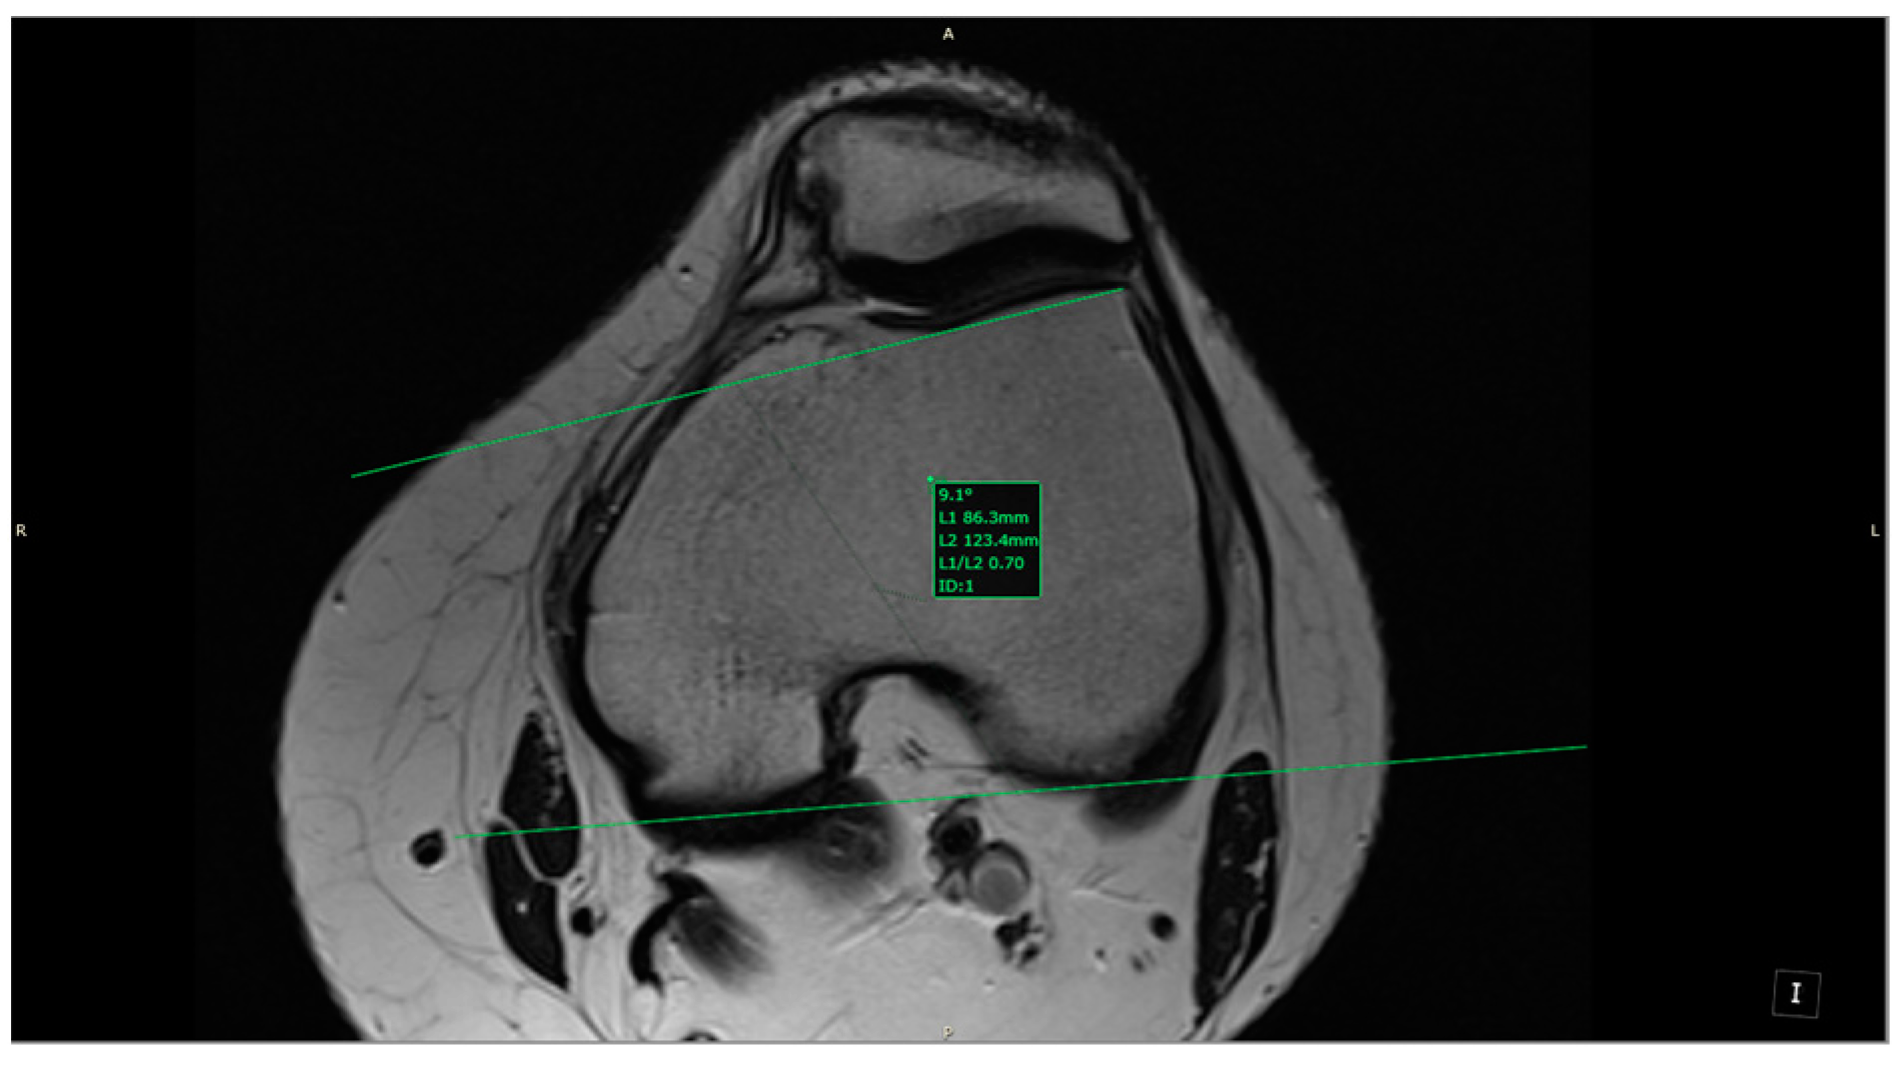

- LTI: inclination angle between the lateral femoral trochlea on the most proximal axial slice containing trochlear cartilage and a posterior condylar tangential line (in the axial plane; Figure 5).

- Trochlear dysplasia: LTI < 11° (in the axial plane).